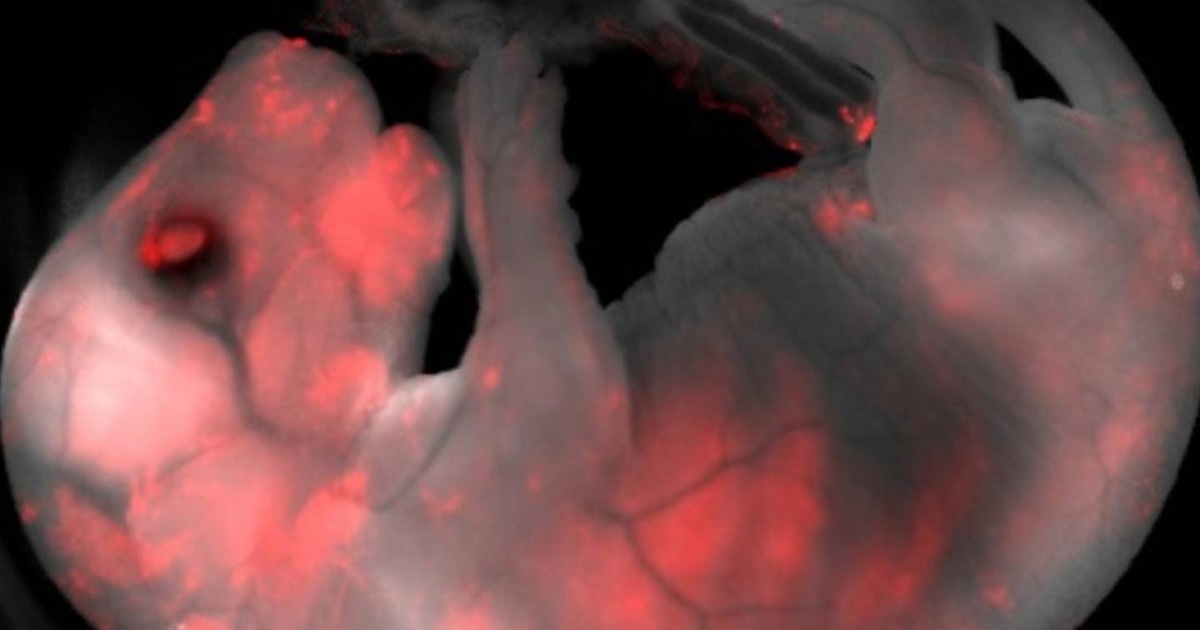

О создании эмбриона-гибрида из клеток свиньи и человека сообщается на страницах журнала "Nature". Ученые рассказали, что для создания химеры они использовали около 1,4 тысяч свиных зародышей, в которые вводились индуцированные стволовые клетки человека. Экспериментальные эмбрионы после этого были подсажены в тела свиноматок, где они смогли успешно развиваться.

Эмбрионы-гибриды из клеток свиньи и человека специалисты "вырастили" до 4-х недель, после чего по этическим соображениям уничтожили. Но эксперимент показал, что в 186 эмбрионах из 1400 смогли прижиться клетки человеческого происхождения, следовательно эти зародыши стали химерами человека и свиньи.